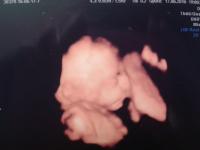

Megkaptam a genetikai UH leletét is, minden rendben van: